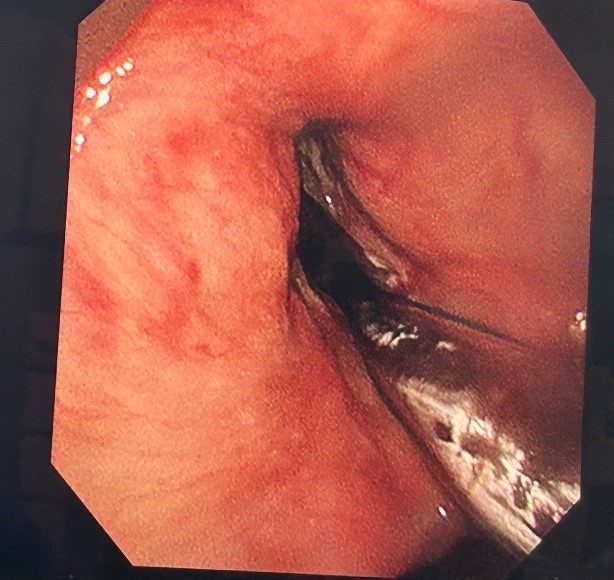

手术室内,气氛紧张而凝重。当支气管镜顺利进入,眼前的景象令人揪心:声门处管腔狭窄程度高达95%,巨大的白色肿物如同巨石般堵塞其中,表面光滑却质地坚硬。医疗团队沉着应对,先予圈套器多次圈套电切治疗,同时进行活检,样本送检常规病理。在精细操作下,声门得以部分暴露。在李健主任带领下的麻醉团队支持配合下,气管插管辅助通气。后续耳鼻喉科宋升桥主任凭借其深厚的专业功底,在支撑喉内镜下行喉部肿瘤等离子切除术。每一次操作都精准无误,每一个步骤都紧密衔接。在团队的共同努力下,肿物被逐步、分段切除,声带及喉室得以充分暴露,术后喉空间完全开放,管腔恢复通畅,如同被疏通的河道,重新恢复了生机,同时,凭借团队精湛的医术与充分完善的术前准备,避免气管切开带来的痛苦。术中患者生命体征始终保持稳定,术后患者呼吸明显顺畅,当晚便酣然入睡,目前患者正在住院恢复当中。